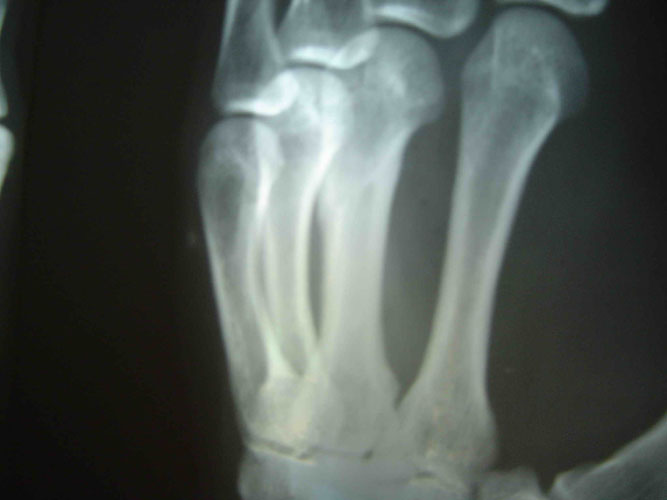

因为剧痛,邢加秋挣脱用手去挡,抬起的手却被犯人李素安抡了一棒,邢眼前一黑晕了过去,不法犯人们又把他打醒,强制他站起来,这时,邢加秋的手背肿得象个馒头,手心青紫,不能动,感觉骨头象断了一样。第二天,犯人李素安、犯人金永军说邢加秋罚站时动摇,对他又一顿毒打,李素安阴险地冲着邢加秋受伤的手砍了一掌,邢大叫一声痛得坐在地上,此后邢家秋的手剧烈疼痛不敢动。(2005年6月在沈阳第一监狱拍的X光片子显示邢加秋左手中指骨折)

这已是两年后的照片了,但仍然清晰可见左手中指骨折的痕迹